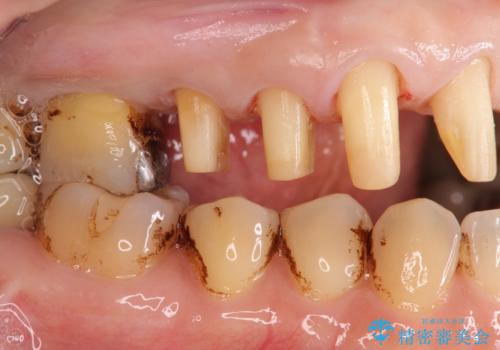

歯周病に対する全体治療

- 近医で「重度の歯周病です、入れ歯にする必要がある。」、と言われ入れ歯以外の方法がないか相談にみえられました。

再生治療、歯周外科を行うことで歯周病治療を行い、残すことのできる歯の歯周環境を整える。

残すことのできない歯は抜去したのち骨造成を含めたインプラント治療を行い、しっかりとした咬合関係を確立していきます。

治療期間はかかりましたが、しっかりと歯周病治療・インプラント治療を行ったおかげで歯周病の状態は非常に良くなり、安定した咬合関係を確立することができました。